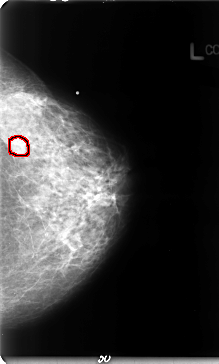

B_3072_1.LEFT_CC

LEFT_CC LINES 4720 PIXELS_PER_LINE 2840 BITS_PER_PIXEL 12 RESOLUTION 50 OVERLAY

FILE: B_3072_1.LEFT_MLO.OVERLAY

TOTAL_ABNORMALITIES 1

ABNORMALITY 1

LESION_TYPE MASS SHAPE IRREGULAR MARGINS OBSCURED-ILL_DEFINED

ASSESSMENT 3

SUBTLETY 3

PATHOLOGY MALIGNANT

TOTAL_OUTLINES 1

BOUNDARY